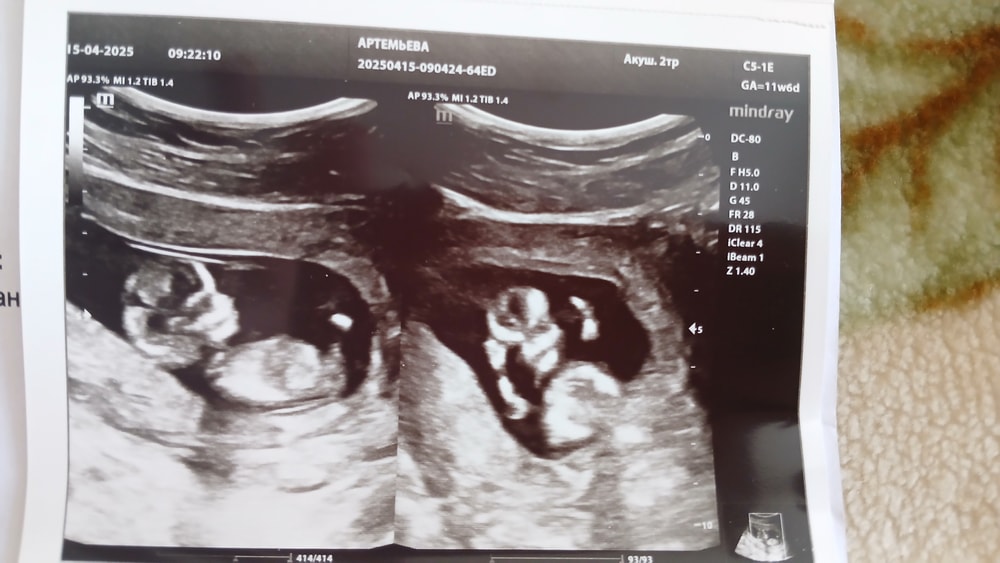

Анализы, скринингиВсем привет!) Сделала скрининг платно, всё в норме,малыш опережает на целую неделю🤯 сегодня по месячным 11+6, по узи по итогу 12+5. Шевелился,ворочался во всю😍 Чудо🤍🫶 Результаты крови придут завтра в течение дня,думаю там тоже всё отлично!)

Тут мы машем ручками около лица😂